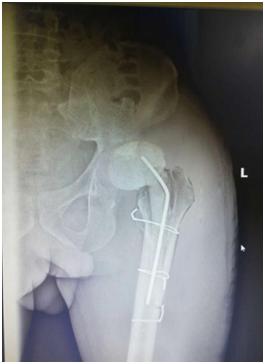

手术前的x光成像

安放旷置器后

经过6天的抗感染治疗后,患者的感染得到控制。2019年12月26日,张先生被送入了手术室,骨科汪军副主任医师与吕彬林主治医师先为张先生行“人工髋关节旷置术”,整个手术用时约3个小时,感染的人工关节假体被顺利取出。并使用双氧水、0.9%生理盐水、聚维酮碘反复冲洗后放入万古霉素骨水泥间隔器占位